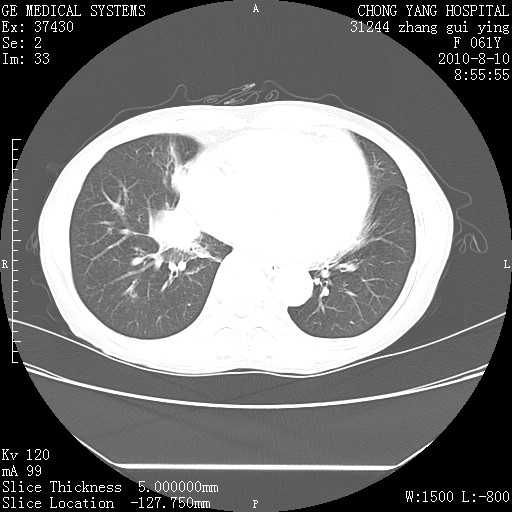

标题: CT28314:F61Y胸部增强,发热咳嗽一周入院,后面的为一周前平 [打印本页]

标题: CT28314:F61Y胸部增强,发热咳嗽一周入院,后面的为一周前平

1、支持考虑右侧中央型肺癌伴右肺中叶节段性不张及下叶支气管黏液痰栓    2、左肺上叶舌段感染。

支持3楼意见,还要考虑:纵隔及肺门淋巴结转移、右侧少量胸腔积液。

确切的说:1:右肺下叶中心型肺癌侵及中叶支气管并中叶不张,纵膈淋巴结转移。2:左肺舌叶炎症。3:右侧胸腔少量积液

块影平扫32hu,动静脉期62-70hu.

1:右肺下叶中心型肺癌侵及中叶支气管并中叶不张,纵膈淋巴结转移。2:左肺舌叶炎症。3:右侧胸腔少量积液。支持!

右肺下叶内基底段近膈不规则肿块,考虑右肺下叶周围型肺癌可能性大。